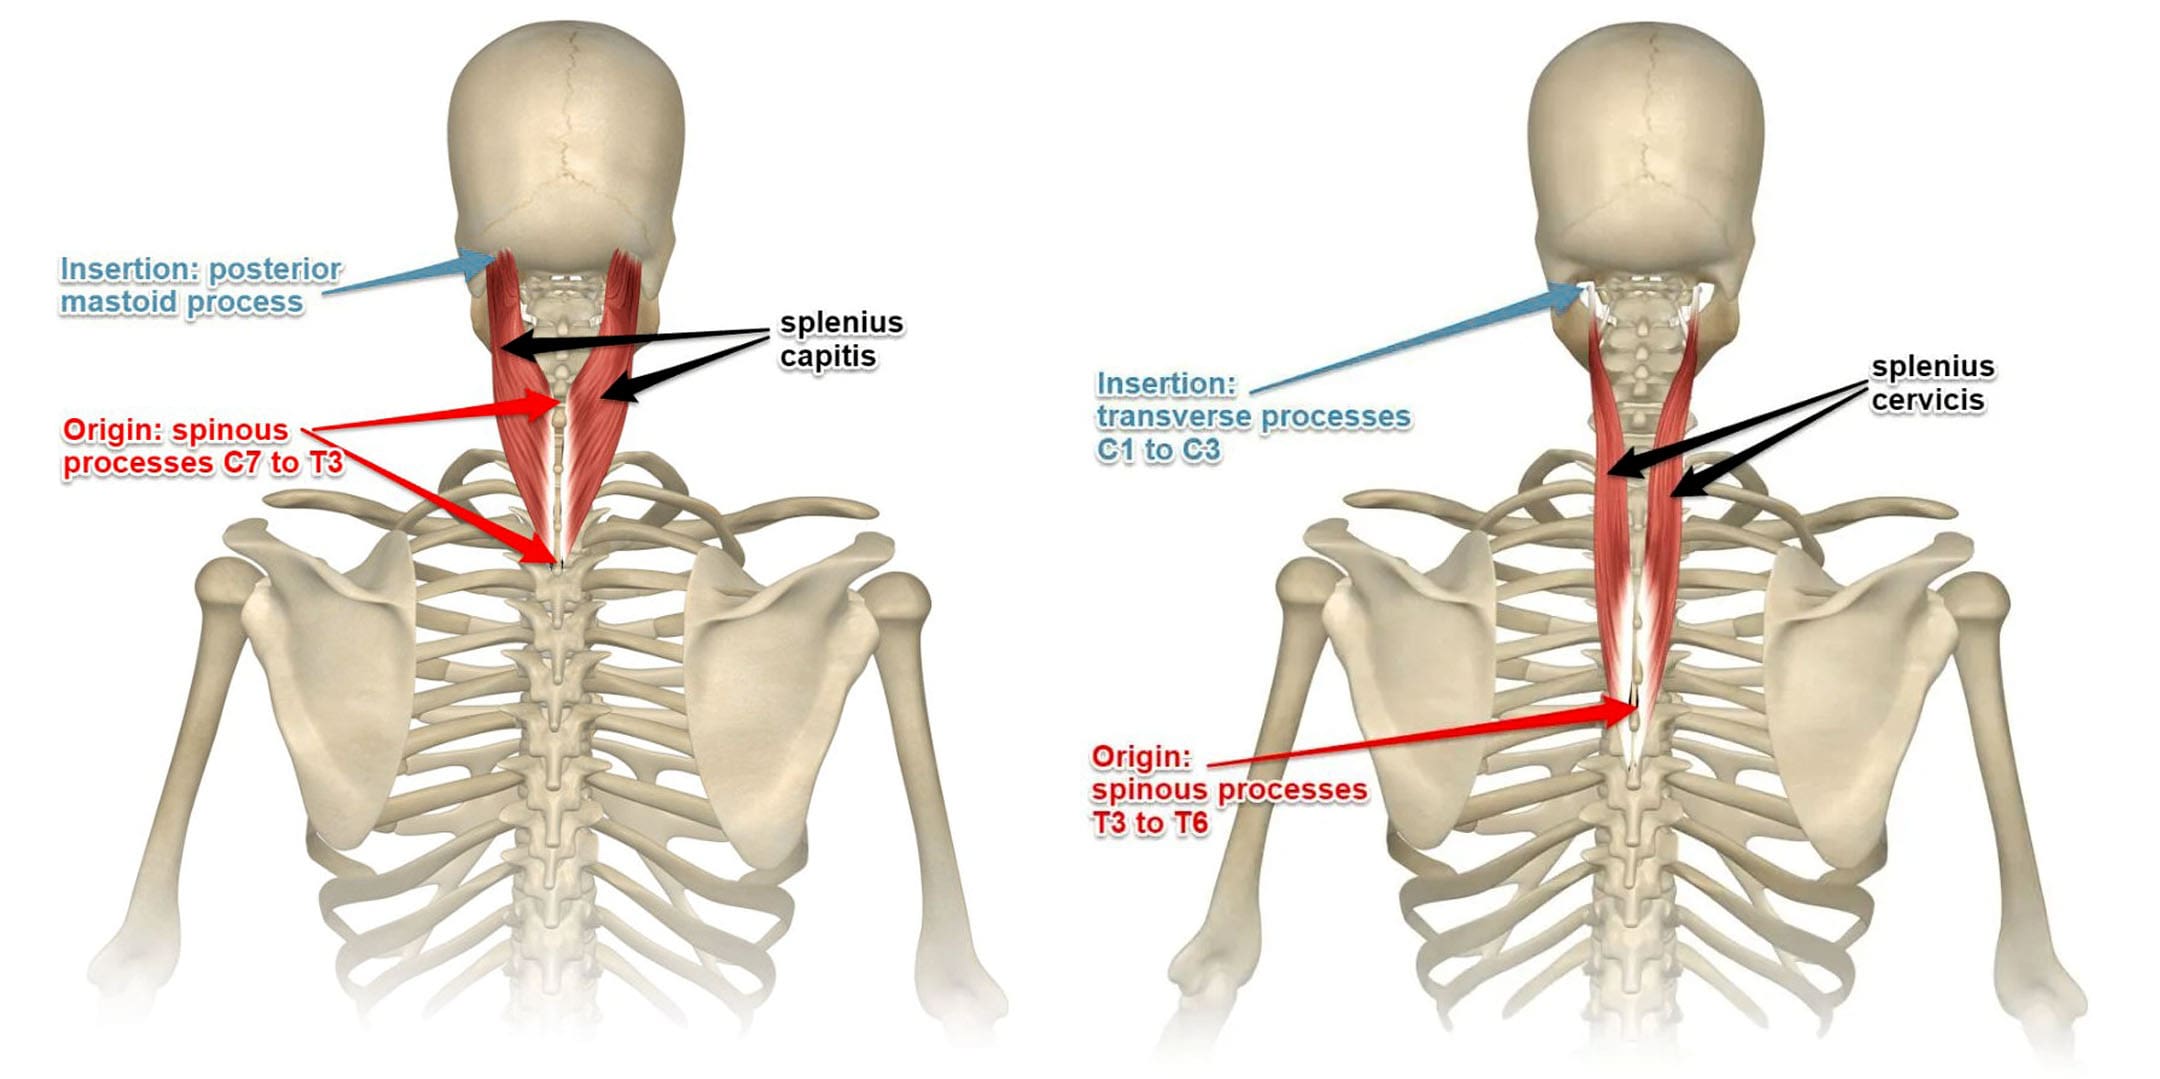

Измерение кифоза грудного отдела: Рентгеновские снимки